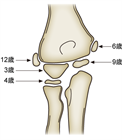

1. 橈骨頭骨折、橈骨頸部骨折の解剖学的特徴を把握する。

1. 橈骨頭骨折、橈骨頸部骨折は上腕骨小頭と橈骨頭が衝突して生じる。

1. 成人では橈骨頭に加え橈骨頚部も骨折しやすいが、小児では多くが橈骨頚部骨折である。